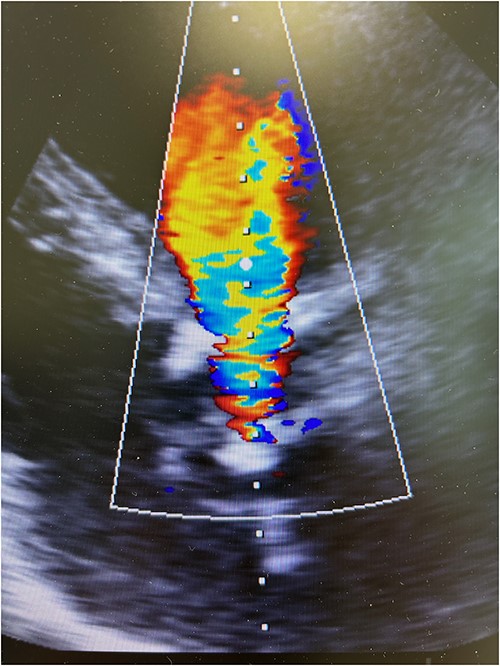

The patient experienced significant dyspnea, increased passiveness, decreased performance, and cardiac echocardiography revealed a destroyed, regurgitant, and stenotic aortic valve prosthesis with myocardial calcification of the left outflow track (Fig. 1) including a peak mean aortic gradient of 76/49 mmHg, Vmax 4.3 m/s and AVA 1.0 cm2 and significant regurgitation (Fig. 2). Minimal mitral valve regurgitation and some coronary artery stenosis were also present.

Preoperative transesophageal echocardiography showing significant regurgitation and stenosis of the aortic valve bioprosthesis.